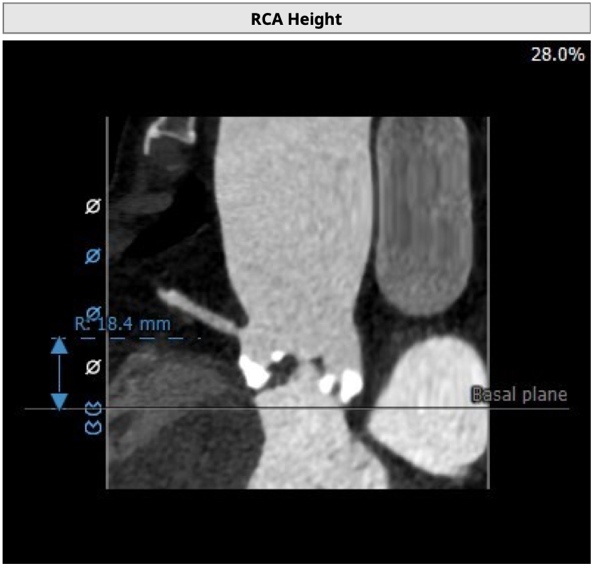

左冠开口高度14.2mm,右冠开口高度18.4mm,左右冠脉高度可。